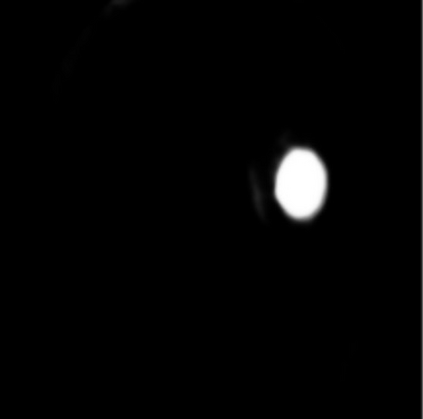

Glaucoma is one of the most severe eye diseases, characterized by rapid progression and leading to irreversible blindness. It is often the case that pathology diagnostics is carried out when the one's sight has already significantly degraded due to the lack of noticeable symptoms at early stage of the disease. Regular glaucoma screenings of the population shall improve early-stage detection, however the desirable frequency of etymological checkups is often not feasible due to excessive load imposed by manual diagnostics on limited number of specialists. Considering the basic methodology to detect glaucoma is to analyze fundus images for the \textit{optic-disc-to-optic-cup ratio}, Machine Learning domain can offer sophisticated tooling for image processing and classification. In our work, we propose an advanced image pre-processing technique combined with an ensemble of deep classification networks. Our \textit{Retinal Auto Detection (RADNet)} model has been successfully tested on Rotterdam EyePACS AIROGS train dataset with AUC of 0.92, and then additionally finetuned and tested on a fraction of RIM-ONE DL dataset with AUC of 0.91.